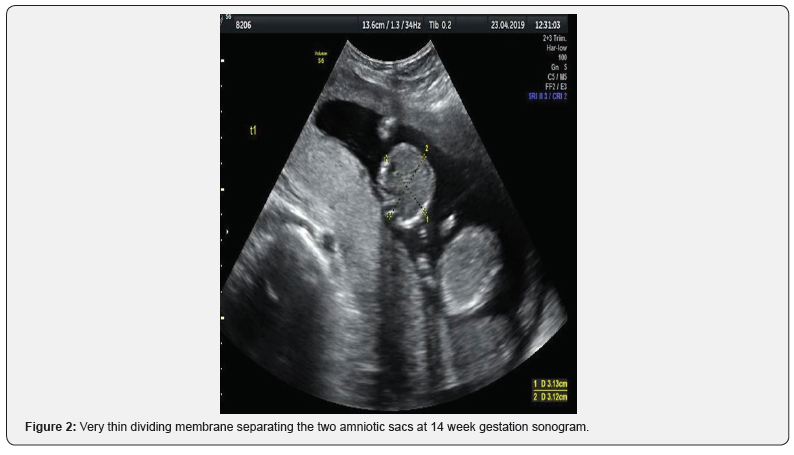

We present a case of a 40-year-old patient (G3, P2) admitted at our Department, presented with a spontaneous twin pregnancy. Prenatal monitoring with ultrasound examination confirmed a monochorionic twin pregnancy (Figure 1). Ultra sonographic follow up was settled every 2 weeks, in order to diagnose potential MCDA complications (Monochorionic Diamniotic Twins). Ultra sonographic evaluation during 14th week of gestation confirmed the existence of the diving membrane, sign of Monochorionic-Diamniotic pregnancies (Figure 2).